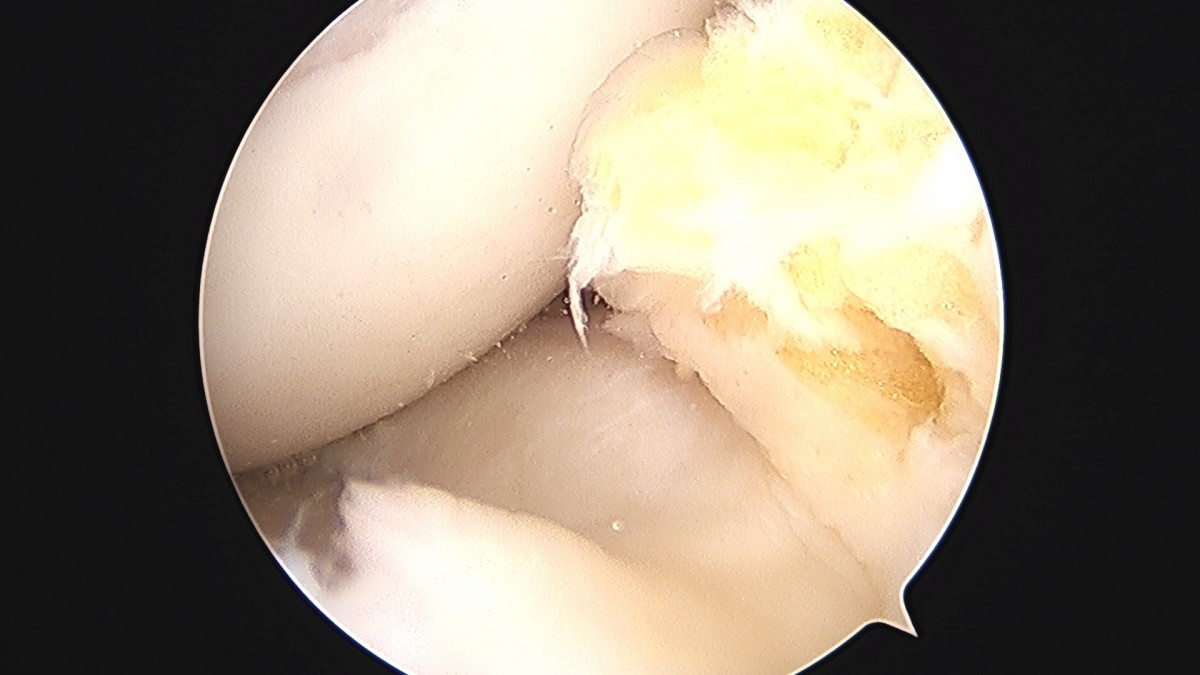

이재상원장님 무릎 반월상 연골판 절제술 강일O 환자

작성자 최고관리자 댓글 0건 조회 372회 작성일 25-09-16 16:12